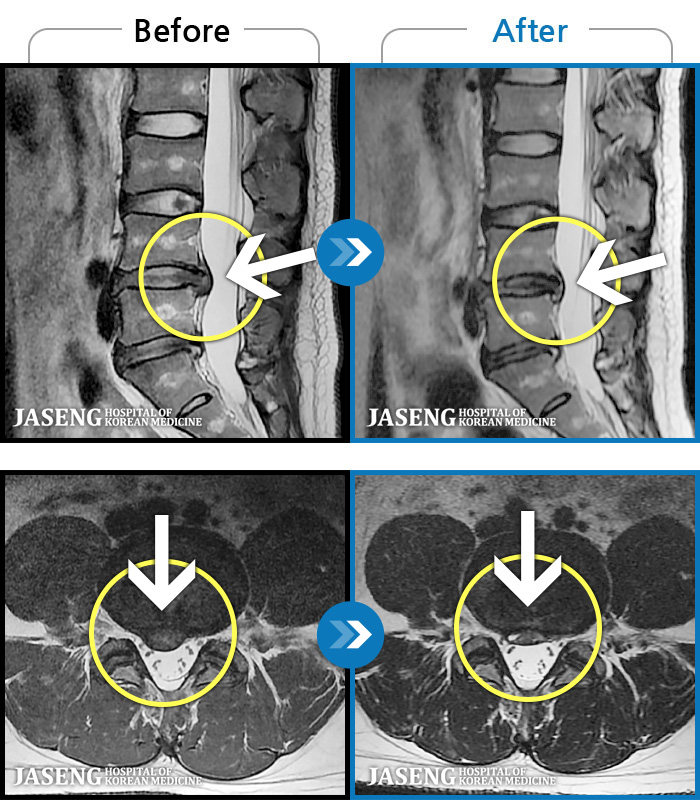

MRI ġ

1,237 MRI ũ ʸ Ȯϼ.